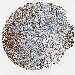

UROTHELIAL CANCER - Protein expressioni

A mouse-over function shows sample information and annotation data. Click on an image to view it in a full screen mode. Samples can be filtered based on level of antibody staining by selecting one or several of the following categories: high, medium, low and not detected. The assay and annotation is described here.

Note that samples used for immunohistochemistry by the Human Protein Atlas do not correspond to samples in the TCGA dataset.

Antibody stainingi

Antibody staining in the annotated cell types in the current human tissue is reported as not detected, low, medium, or high, based on conventional immunohistochemistry profiling in selected tissues. This score is based on the combination of the staining intensity and fraction of stained cells.

Each image is clickable and will lead to virtual microscopy that enables deeper exploration of all samples and also displays staining intensity scores, fraction scores and subcellular localization as well as patient and tissue information for each sample.

Antibody HPA008066

Antibody HPA017330

Antibody CAB000006

Staining

High

Medium

Low

Not detected

Intensity

Strong

Moderate

Weak

Negative

Quantity

>75%

75%-25%

<25%

None

Location

Nuclear

Cytoplasmic/membranous

Cytoplasmic/membranous,nuclear

Urothelial carcinoma, Low grade

Urothelial carcinoma, High grade